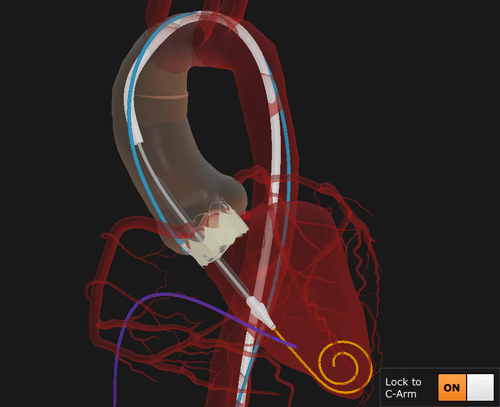

Mentice Aortic Valve Implantation is designed for interventional cardiologists and cardiac/cardiothoracic surgeons who wish to train on transcatheter aortic valve implantation/replacement (TAVI/TAVR). As TAVI volumes increase due to expanding reimbursement and its adoption for younger, low-risk patients, effective training becomes critical to ensure consistent outcomes. This module provides a safe, cost-effective platform for individual instruction or hospital-wide quality improvement programs.

With generic balloon and self-expandable valves, users can explore the nuances of different deployment techniques and adapt to the growing variety of valves on the market. Physicians can refine skills like the cusp overlap technique, deepen their understanding of anatomy, and prepare for the challenges of treating diverse patient profiles—all in a realistic and patient-free environment.

Enables training on balloon- and self-expanding valves for diverse valve support

Improved delivery system for hands-on practice with realistic device handling

Enhances anatomy understanding and deployment accuracy with augmented visualization